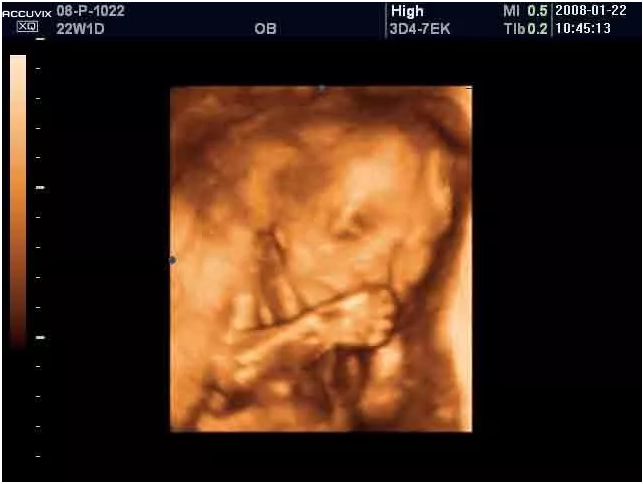

出于这样的吮吸本能,有的宝宝在妈妈肚子里的时候就开始吃手了,父母通过B超就可以看到吃手的画面。这个小动作是宝宝安慰自己的一种方式,而且还可以帮助他在出生后能顺利吸到母乳。